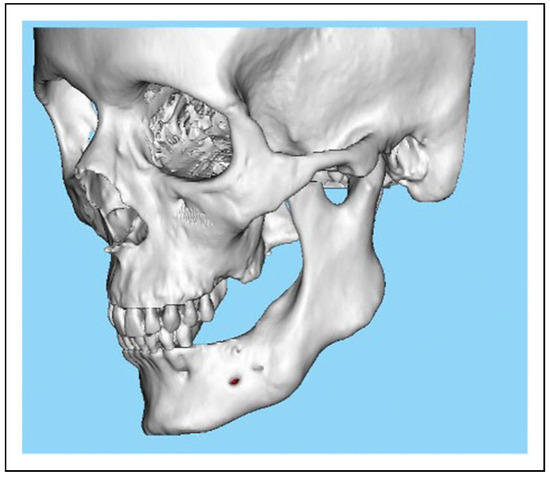

Single-Stage Regime, Patient 10